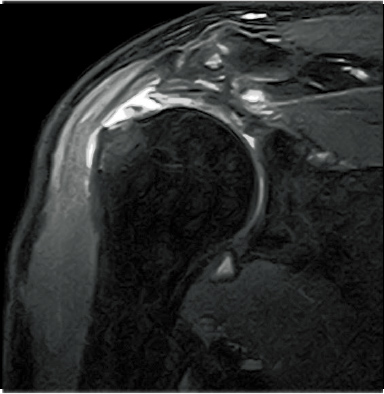

FatSat-PDWI